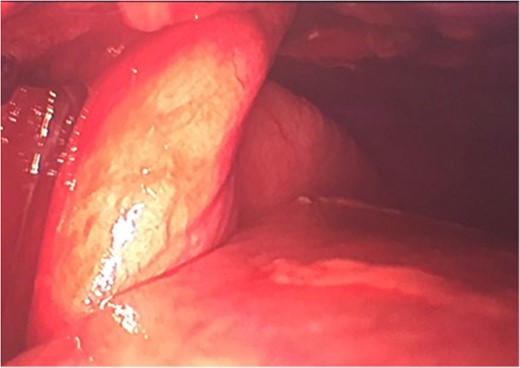

Due to the macroscopic appearance of ischemia and venous congestion of the involved lung tissue, a non-anatomic lingular resection using 60 mm Echelon Flex Stappler® was performed (Fig. 3) as well as a chest washout.

Wedge resection of ischemic lung through chest wall herniation.